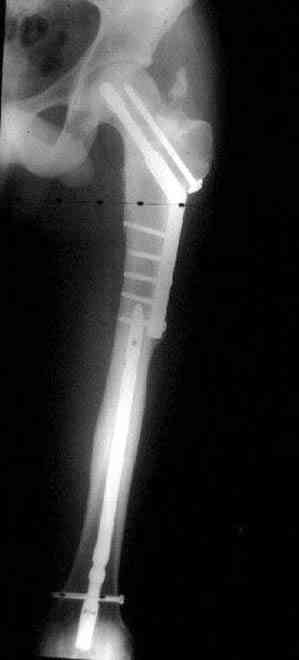

Несмотря на пессимистические прогнозы, у молодых

коррегирующая вальгусная остеотомия является более

приемлемым.

Представленные случаи доказательства тому, что еще

имеется резервы на восстановление даже у 5-6 месячных ложных суставов шейки.